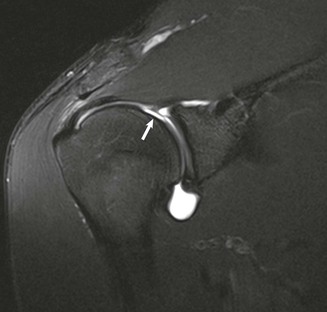

Although conventional MRI is established as the imaging modality of choice in the evaluation of shoulder impingement syndrome, MRA is accepted as the method of choice for the evaluation of glenohumeral instability.22,23 Many of the lesions associated with instability are subtle and may undergo partial healing. This situation, coupled with the fact that the normal anatomic structures of the shoulder lie in close proximity, can make the diagnosis of these lesions difficult even with high-quality conventional MRI.58-62 MRA, on the other hand, is performed by distending the joint with fluid (saline solution or dilute gadolinium), which more accurately depicts subtle labral tears, cartilage and ligamentous abnormalities, and partial-thickness tears of the undersurface of the rotator cuff. The standard injection technique for MRA of the shoulder is described in previous sections. About 12 to 14 mL of gadolinium diluted 1 : 200 with normal saline solution or 1% lidocaine is injected. Imaging protocols vary, but a standard set of imaging sequences typically includes T1-weighted images with frequency-selective fat saturation in the axial, oblique sagittal, and oblique coronal planes. The T1-weighted images have a high signal/noise ratio, resulting in the anatomic detail that is critical in detecting the subtle lesions associated with glenohumeral instability. A T2-weighted sequence performed in the oblique coronal plane is the most important sequence for depicting rotator cuff abnormalities. A T2-weighted sequence may also be helpful in detecting other pathologic processes, such as a paralabral cyst or bone marrow edema (Fig. 44-7, A and B). The ABER view may be added to the standard imaging protocol for any patient thought to have an anterior labral pathologic process.54

MRI and MRA are the main imaging modalities used in the evaluation of a patient with glenohumeral instability.22,23 Even with 3-tesla magnets, MRA demonstrated superior sensitivity compared with routine MRI in a study of 150 consecutive examinations for detecting SLAP lesions and labral tears.138 Joint distention with fluid outlines and separates the normal anatomic structures, allowing more accurate depiction of subtle lesions (Fig. 44-36). CT imaging with sagittal and coronal reconstructions remains the study of choice for detecting and depicting the size and location of a fracture fragment of the anteroinferior glenoid rim (see Fig. 44-4), which can be useful in presurgical planning in patients with large osseous Bankart lesions. As previously stated, MDCT arthrography is accurate for detecting instability lesions and very useful for patients who cannot undergo MRA or lack access to MRI services. The addition of MRI stress views, such as the ABER view (see Fig. 44-37, C), may improve visualization of a nondisplaced tear in the anterior inferior labrum.54